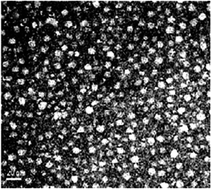

The objectives of this study were to extract curcuminoid from Curcuma longa L. (C. longa), a vital medicinal plant demonstrated to possess many biological activities, and prepare the curcuminoid extract and microemulsion for studying the inhibition mechanism of HT-29 colon cancer cells. Results showed that a total of 3 curcuminoids including curcumin, demethoxycurcumin (DMC) and bisdemethoxycurcumin (BDMC), were separated within 10 min by using an Eclipse XDB-18 column and a gradient mobile phase of 0.1% formic acid solution (A) and acetonitrile (B). The curcuminoid microemulsion composed of soybean oil, Tween 80, ethanol and water was prepared with a high stability and mean particle size of 10.9 nm, zeta-potential of −65.2 mV and encapsulation efficiency of 85.7%. Both curcuminoid extract and microemulsion were effective in inhibiting HT-29 cell growth with the IC50 being 3.83 and 2.51 μg mL−1 after 24 h incubation, respectively, but further reduced to 2.23 and 1.94 μg mL−1, after 48 h incubation. Both treatments could decrease the proportion of both viable and necrosis cells and increase the proportion of both early and late apoptosis cells in a dose-dependent manner, with the cell cycle arrested at the S phase. Also, both treatments could up-regulate p53 expression and down-regulate cyclin A and CDK2 expressions through a p21-independent pathway. In addition, the expressions of Bax and cytochrome C as well as the activities of caspase-8, caspase-9 and caspase-3 increased for the curcuminoid extract, while the curcuminoid microemulsion showed the same trend with the exception that an insignificant change (p > 0.05) in Bax expression was observed. Collectively, this study demonstrated that the curcuminoid microemulsion prepared from C. longa may possess great potential for the treatment of colon cancer in the future.